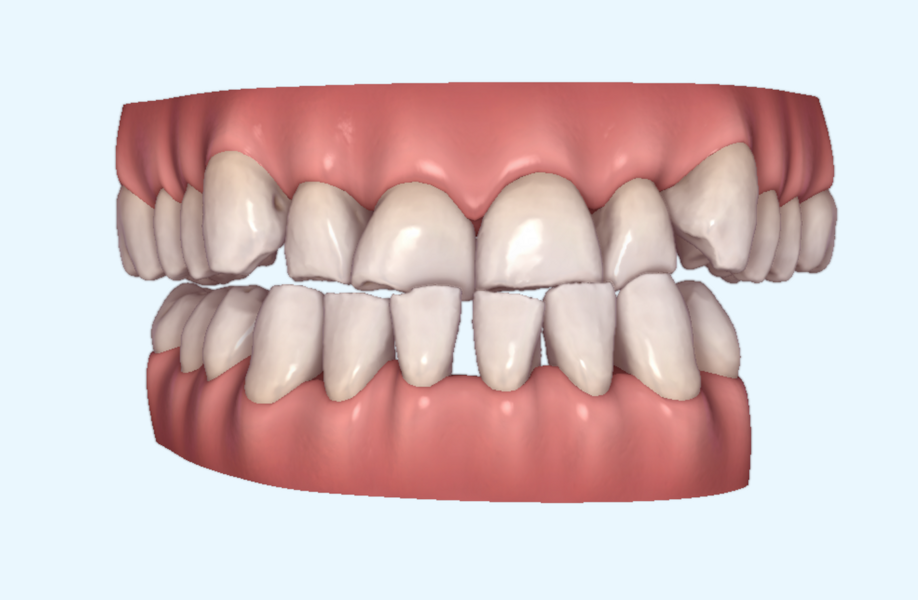

This patient, like all patients requiring interdisciplinary rehabilitation, had to first undergo periodontal treatment and caries restoration (Fig. 17). At the same time, it was important to rehabilitate swallowing with Froggymouth and relax the masticatory muscles and relieve the TMJs with an occlusal device. We could then study the orthodontic treatment plan using Invisalign ClinCheck (Align Technology) and showed the treatment plan to the interdisciplinary team and to the patient (Fig. 18). We were then able to create the correct sequence of orthodontic treatment, bone augmentation and implant surgery needed for the posterior edentulous spaces.

After the first phase of aligner treatment, we had achieved better inter-arch coherence, better maxillary arch expansion, and some space for improving the anterior tooth proportions restoratively (Fig. 19). We then temporarily restored the anterior teeth directly with composite, closing the spaces, improving the tooth proportions and further increasing the maxillary arch expansion (Fig. 20). We used restorative arch expansion to reduce the orthodontic destabilisation of the teeth to achieve the correct inter-arch coherence and retain the teeth in the cortical bone.38 A refinement aligner phase was undertaken to improve the final alignment of the gingival zenith and to improve the inter-arch coherence (Fig. 21). The periods of the first orthodontic phase and of the refinement were used to augment the mandibular and maxillary bone and to place the implants (Fig. 22). At the end of the orthodontic treatment, the case was finalised with ceramic veneers in the anterior area and temporary restorations on the implants in the posterior area (Figs. 23–26).